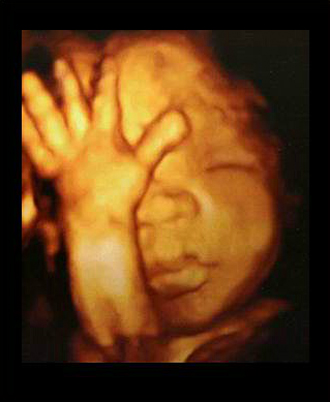

- 4차원 후기 정밀 초음파 (26~28주)

- 필수 검사

- 산전진찰 및 복부 초음파 (1회/2주)

- 막달 산모 종합 검사 (35~36주)

- 태동검사 (34~36주)

- 산전진찰 및 복부 초음파 (1회/1주)

- 태동(태아안녕) 검사 (필요시)

- 단백뇨 검사 (필요시)

- 분만법에 대한 상담